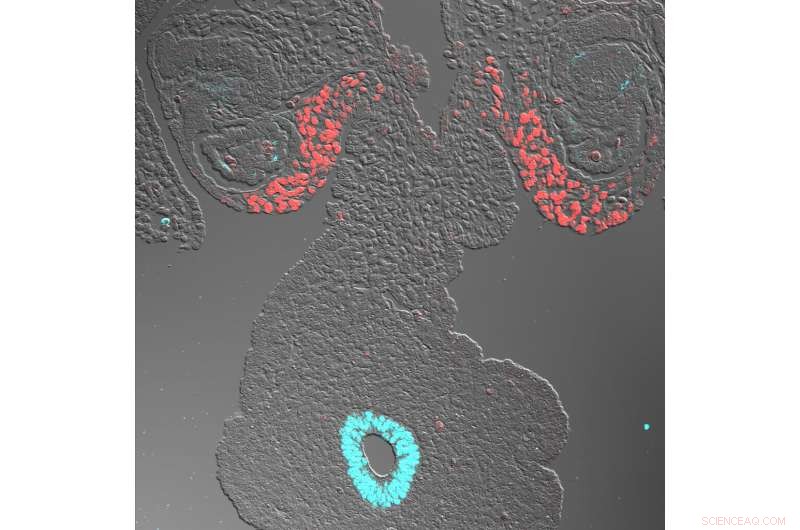

The adrenal glands, which pump out crucial hormones, develops differently in mice compared to primates, including humans, according to new research led by the School of Veterinary Medicine. At at early stage of development, the primate adrenogenic coelomic epithelium, which eventually gives rise to the adrenal glands, expresses genes (NR5A1 in red, and GATA1 in blue) in a pattern that diverged with expectations. Credit: Kotaro Sasaki

Using immunofluorescence and in situ hybridization analyses, in which markers enable scientists to track cells' descendants, Sasaki and his team found that primate CE expressed different genes than mouse CE. Whereas mice expressed the WT1, GATA4, and NR5A1 genes within the adrenogonadal primordium, primates did not express GATA4 in a parallel stage of development, a surprise to the researchers.

What's more, while one portion of the primate CE led to the gonadal precursor, the other developed into the adrenal gland precursors, a division that wasn't present in mice.